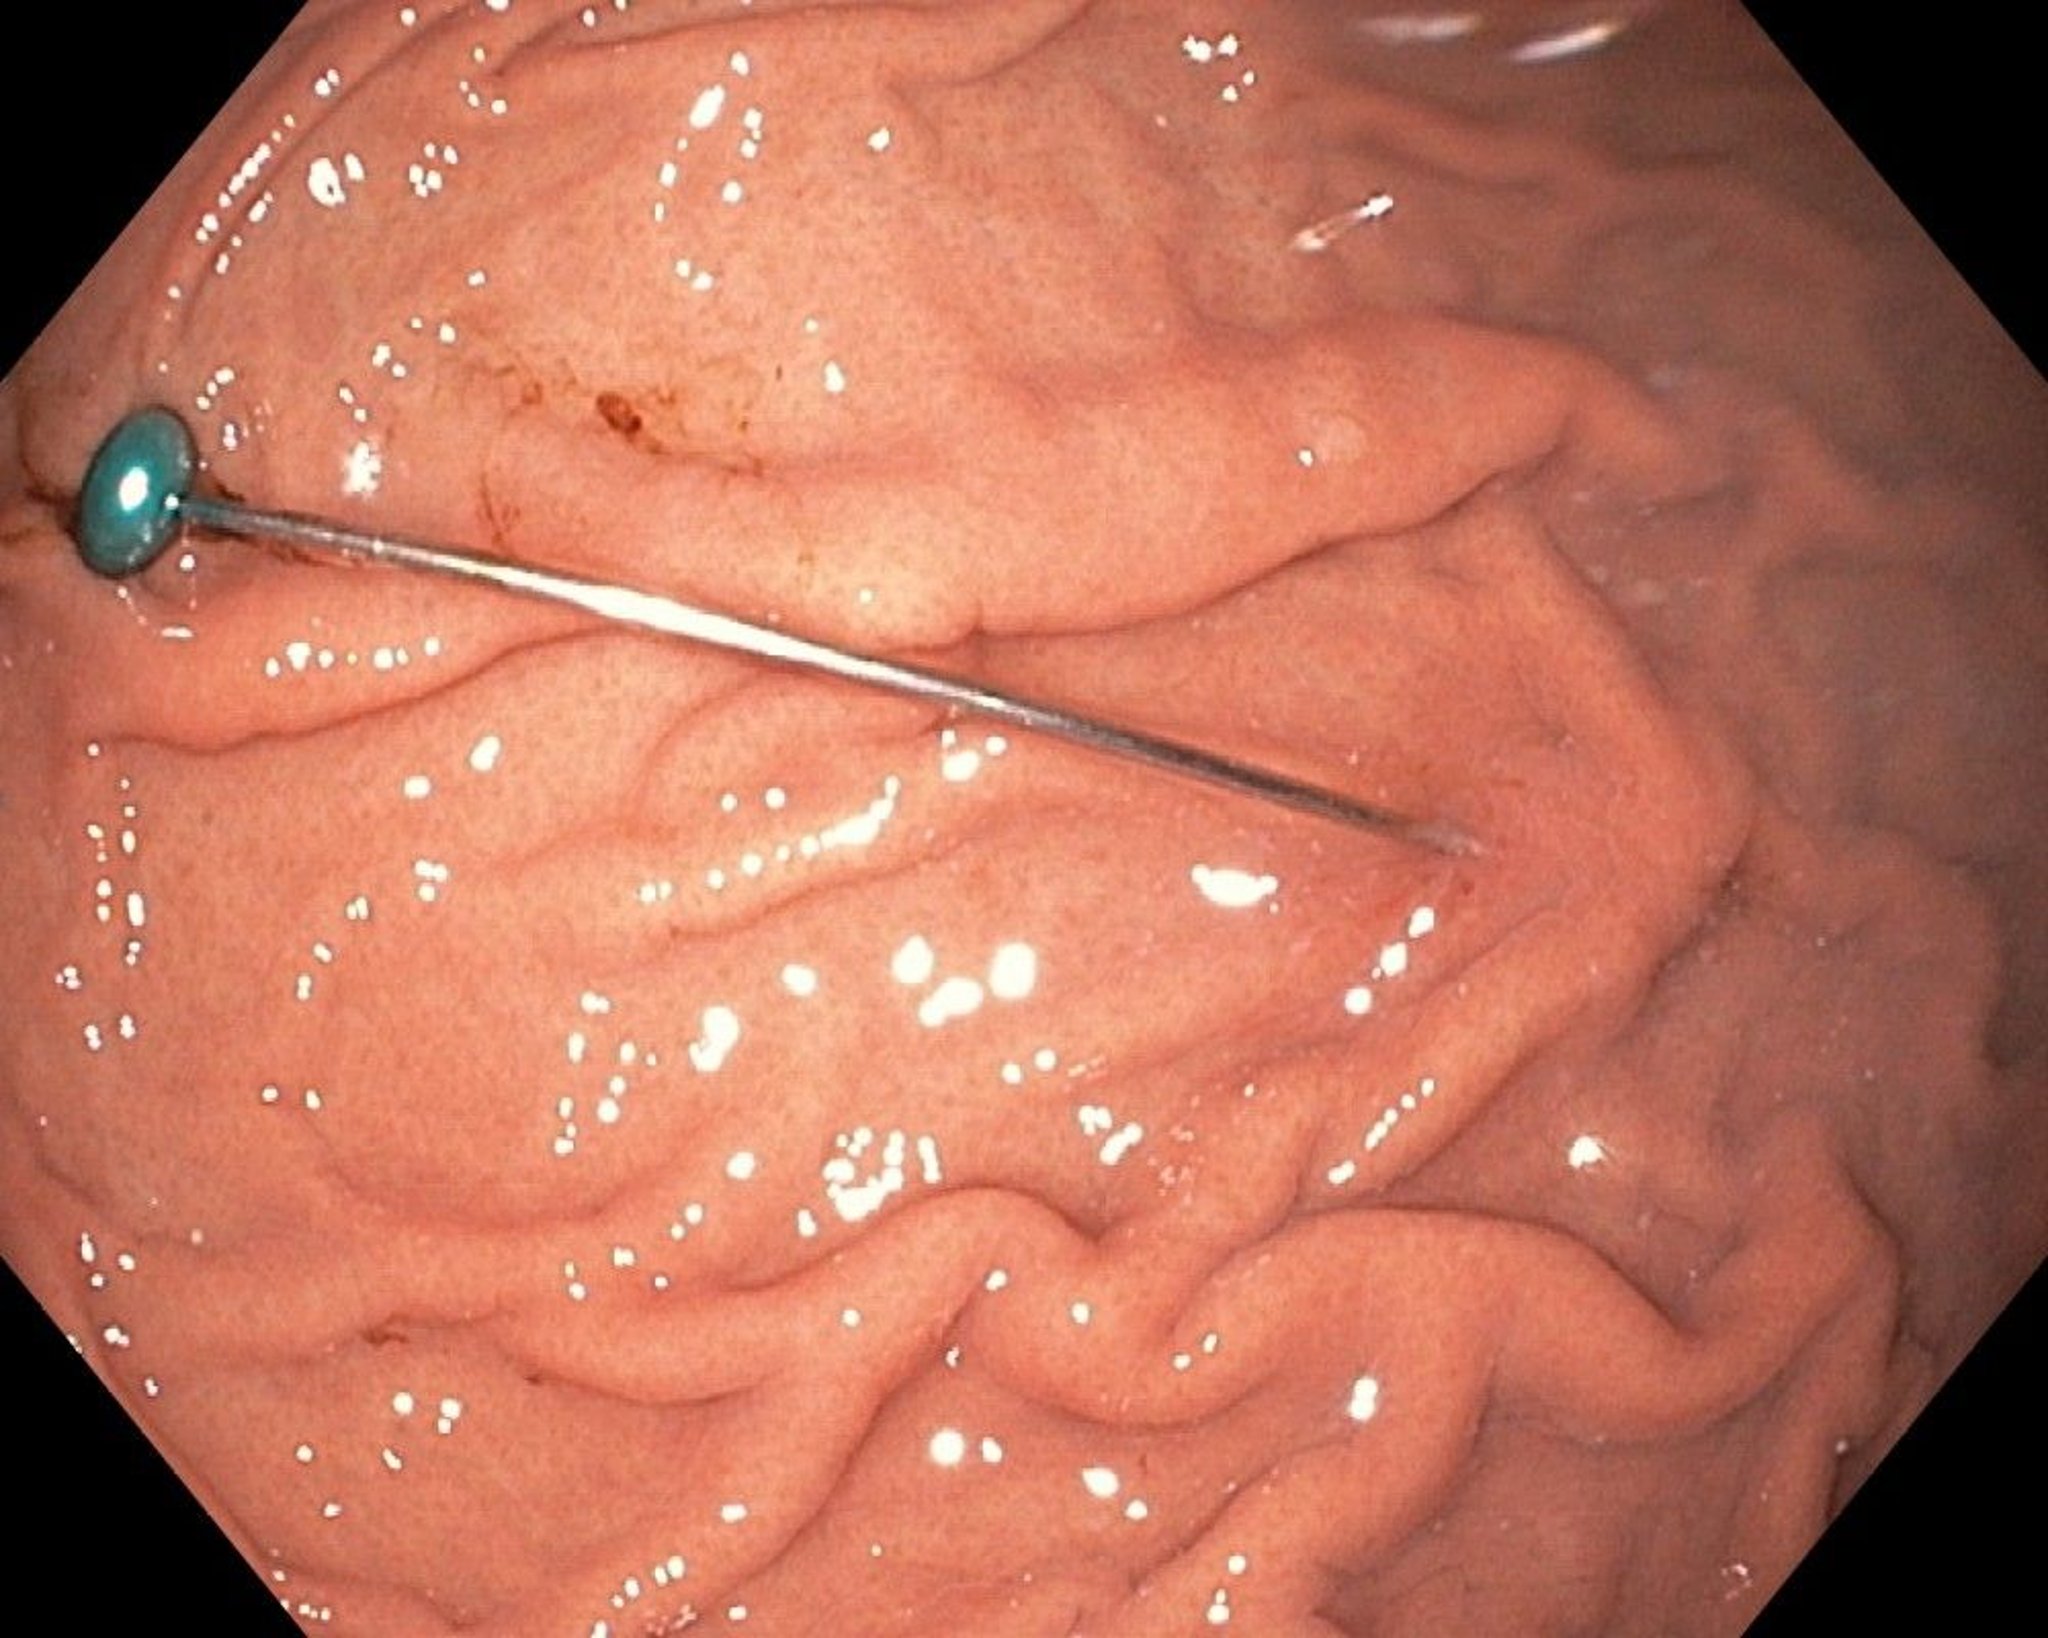

Foreign Body in the Stomach (Endoscopy)

This endoscopic image shows a sharp foreign body in the stomach.

Image provided by Uday Shankar, MD.